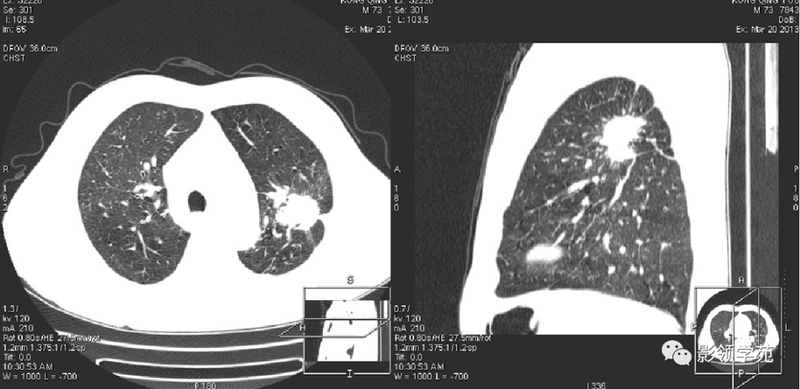

(1)较大含空洞性肿块,洞壁较厚,大于15mm,空洞外壁有分叶、毛刺,洞壁凹凸不平有壁结节,增强可见不规则强化,周围未见明显卫星病灶时,首先考虑周围型肺癌;癌性空洞洞壁一般肺门侧较厚,空洞多偏于外侧,伴有同侧淋巴结肿大更支持肺癌诊断。

(2)空洞病变发生于双肺上叶尖后段、下叶背段,病变周围可见点状、结节状及片状卫星病灶,洞壁组织无明显强化或有包膜线样强化时,考虑结核;结核球的空洞多位于病变的肺门侧,与引流支气管相同,洞内壁一般较光滑。